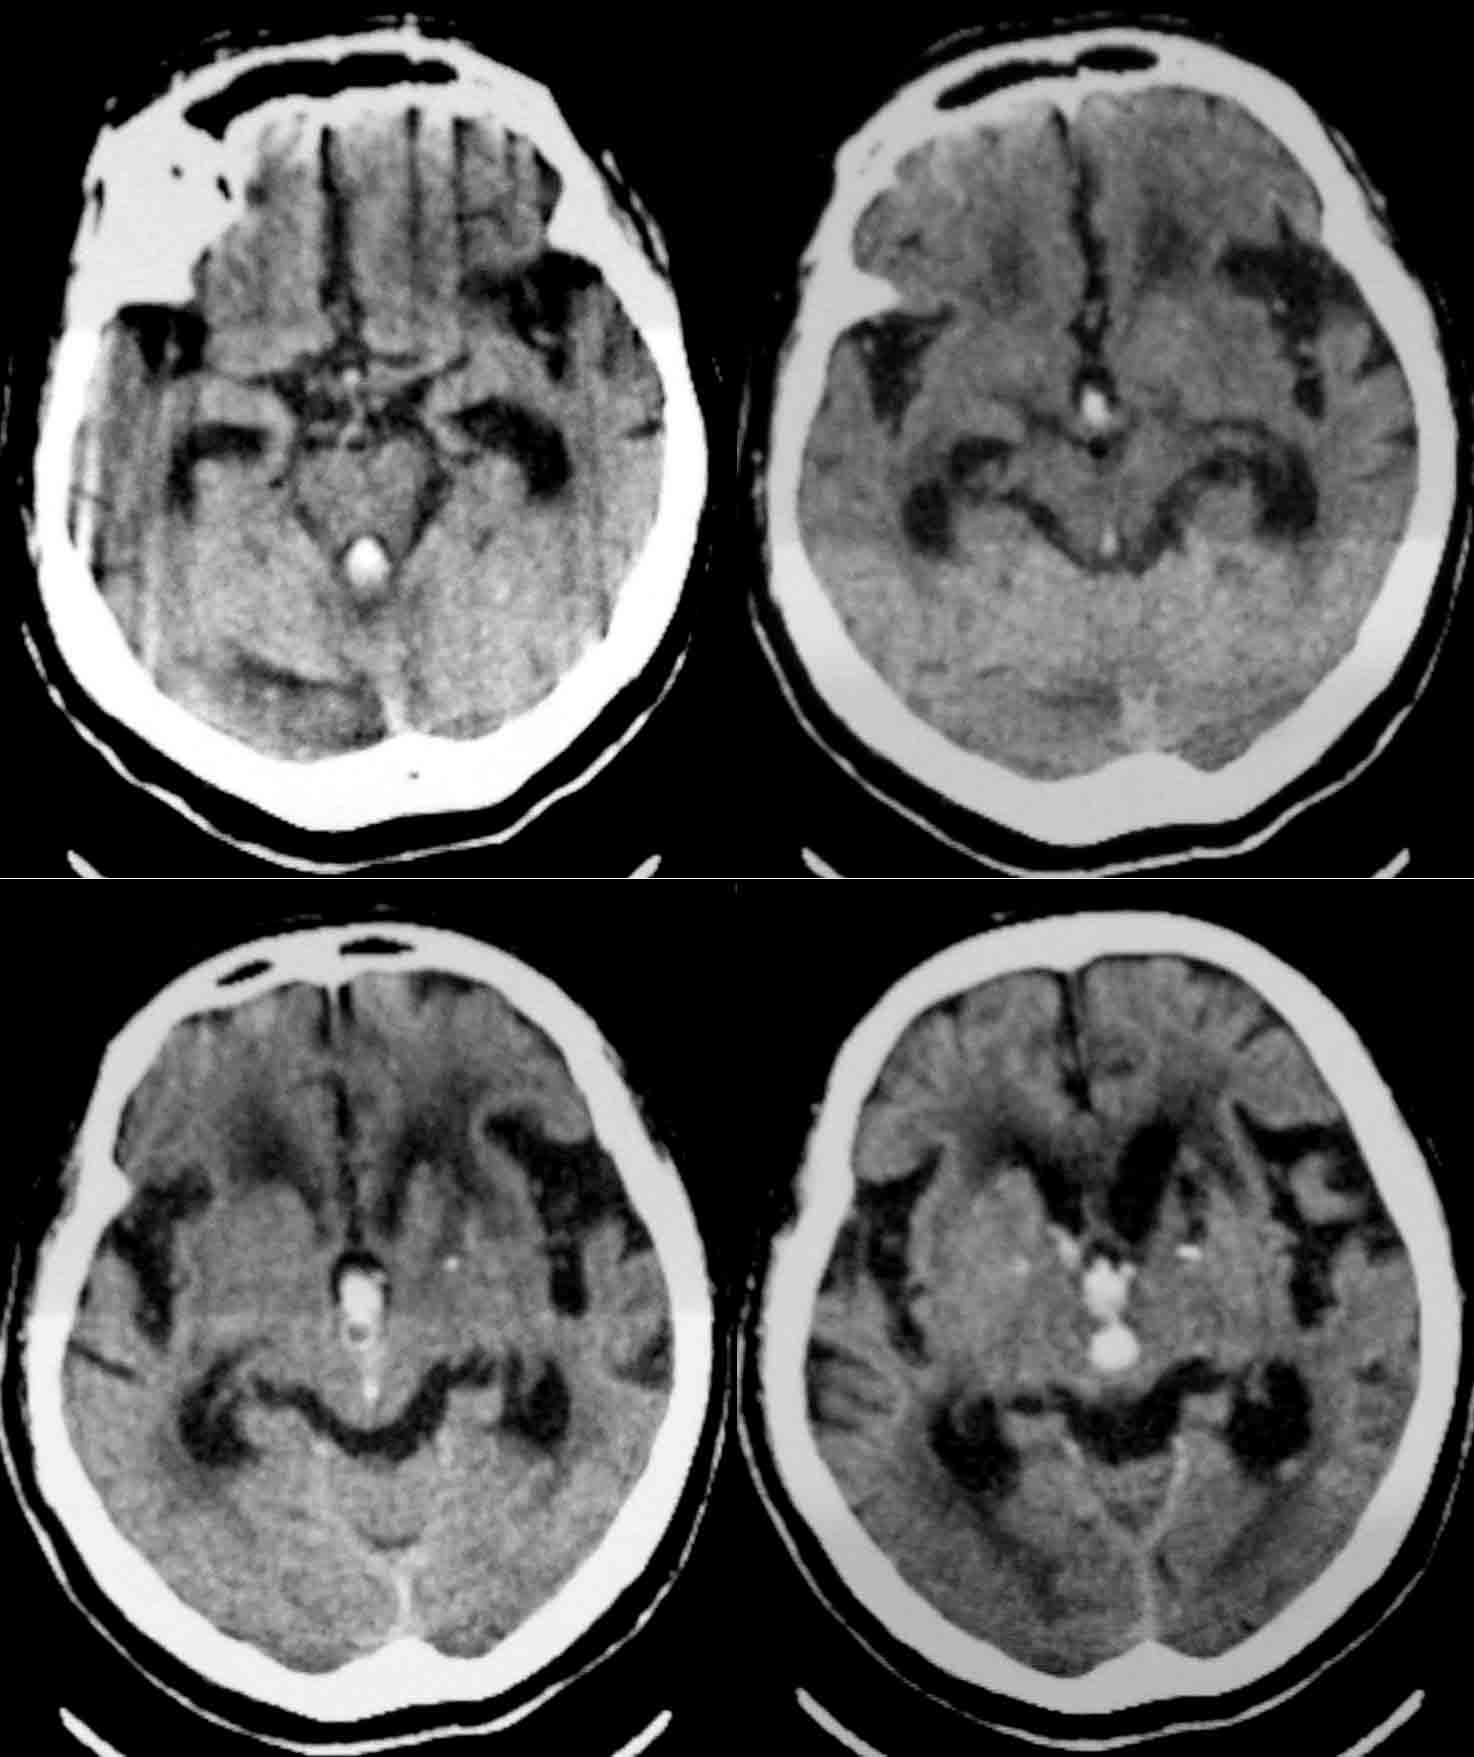

标题: CT24061:女86岁 头痛、呕吐1天 [打印本页]

女86岁 头痛、呕吐1天 请老师们看看,出血的位置是第三、四脑室出血吗?

应该是左侧小脑出血,破入脑室形成铸型。

1.左小脑齿状核出血破入脑室;

2.皮脑。

考虑:1.左小脑齿状核出血破入脑室;

2.脑白质稀疏症伴多发脑软化灶。

应该是左侧小脑出血,破入脑室形成铸型.皮层动脉硬化性脑病。

考虑:1.左小脑齿状核出血破入脑室;2.脑白质稀疏症伴多发脑软化灶。

1)左侧小脑出血破入脑室系统。2)多发性腔隙性脑梗塞。3)脑白质病。4)脑萎缩。